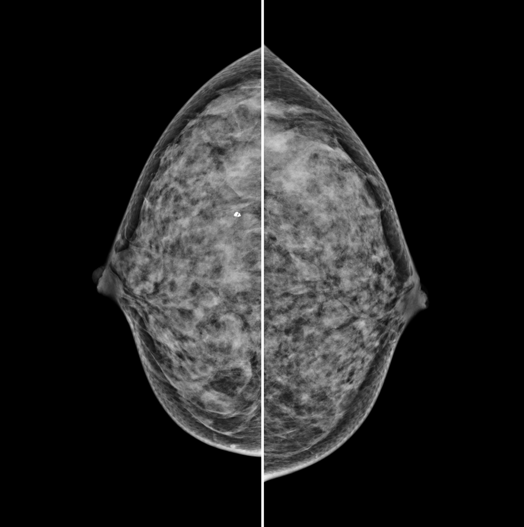

The X-ray tube moves on the breast and takes high-definition, high-resolution images with high contrast from various angles.

The images are reconstructed in 3D to provide accurate information about the location and condition of the lesion.

HESTIA supports "Synthetic 2D" that generates 2D images only by tomography shooting without additional 2D shooting.

GENORAY's know-how that was accumulated for a long time gives the best diagnostic images.